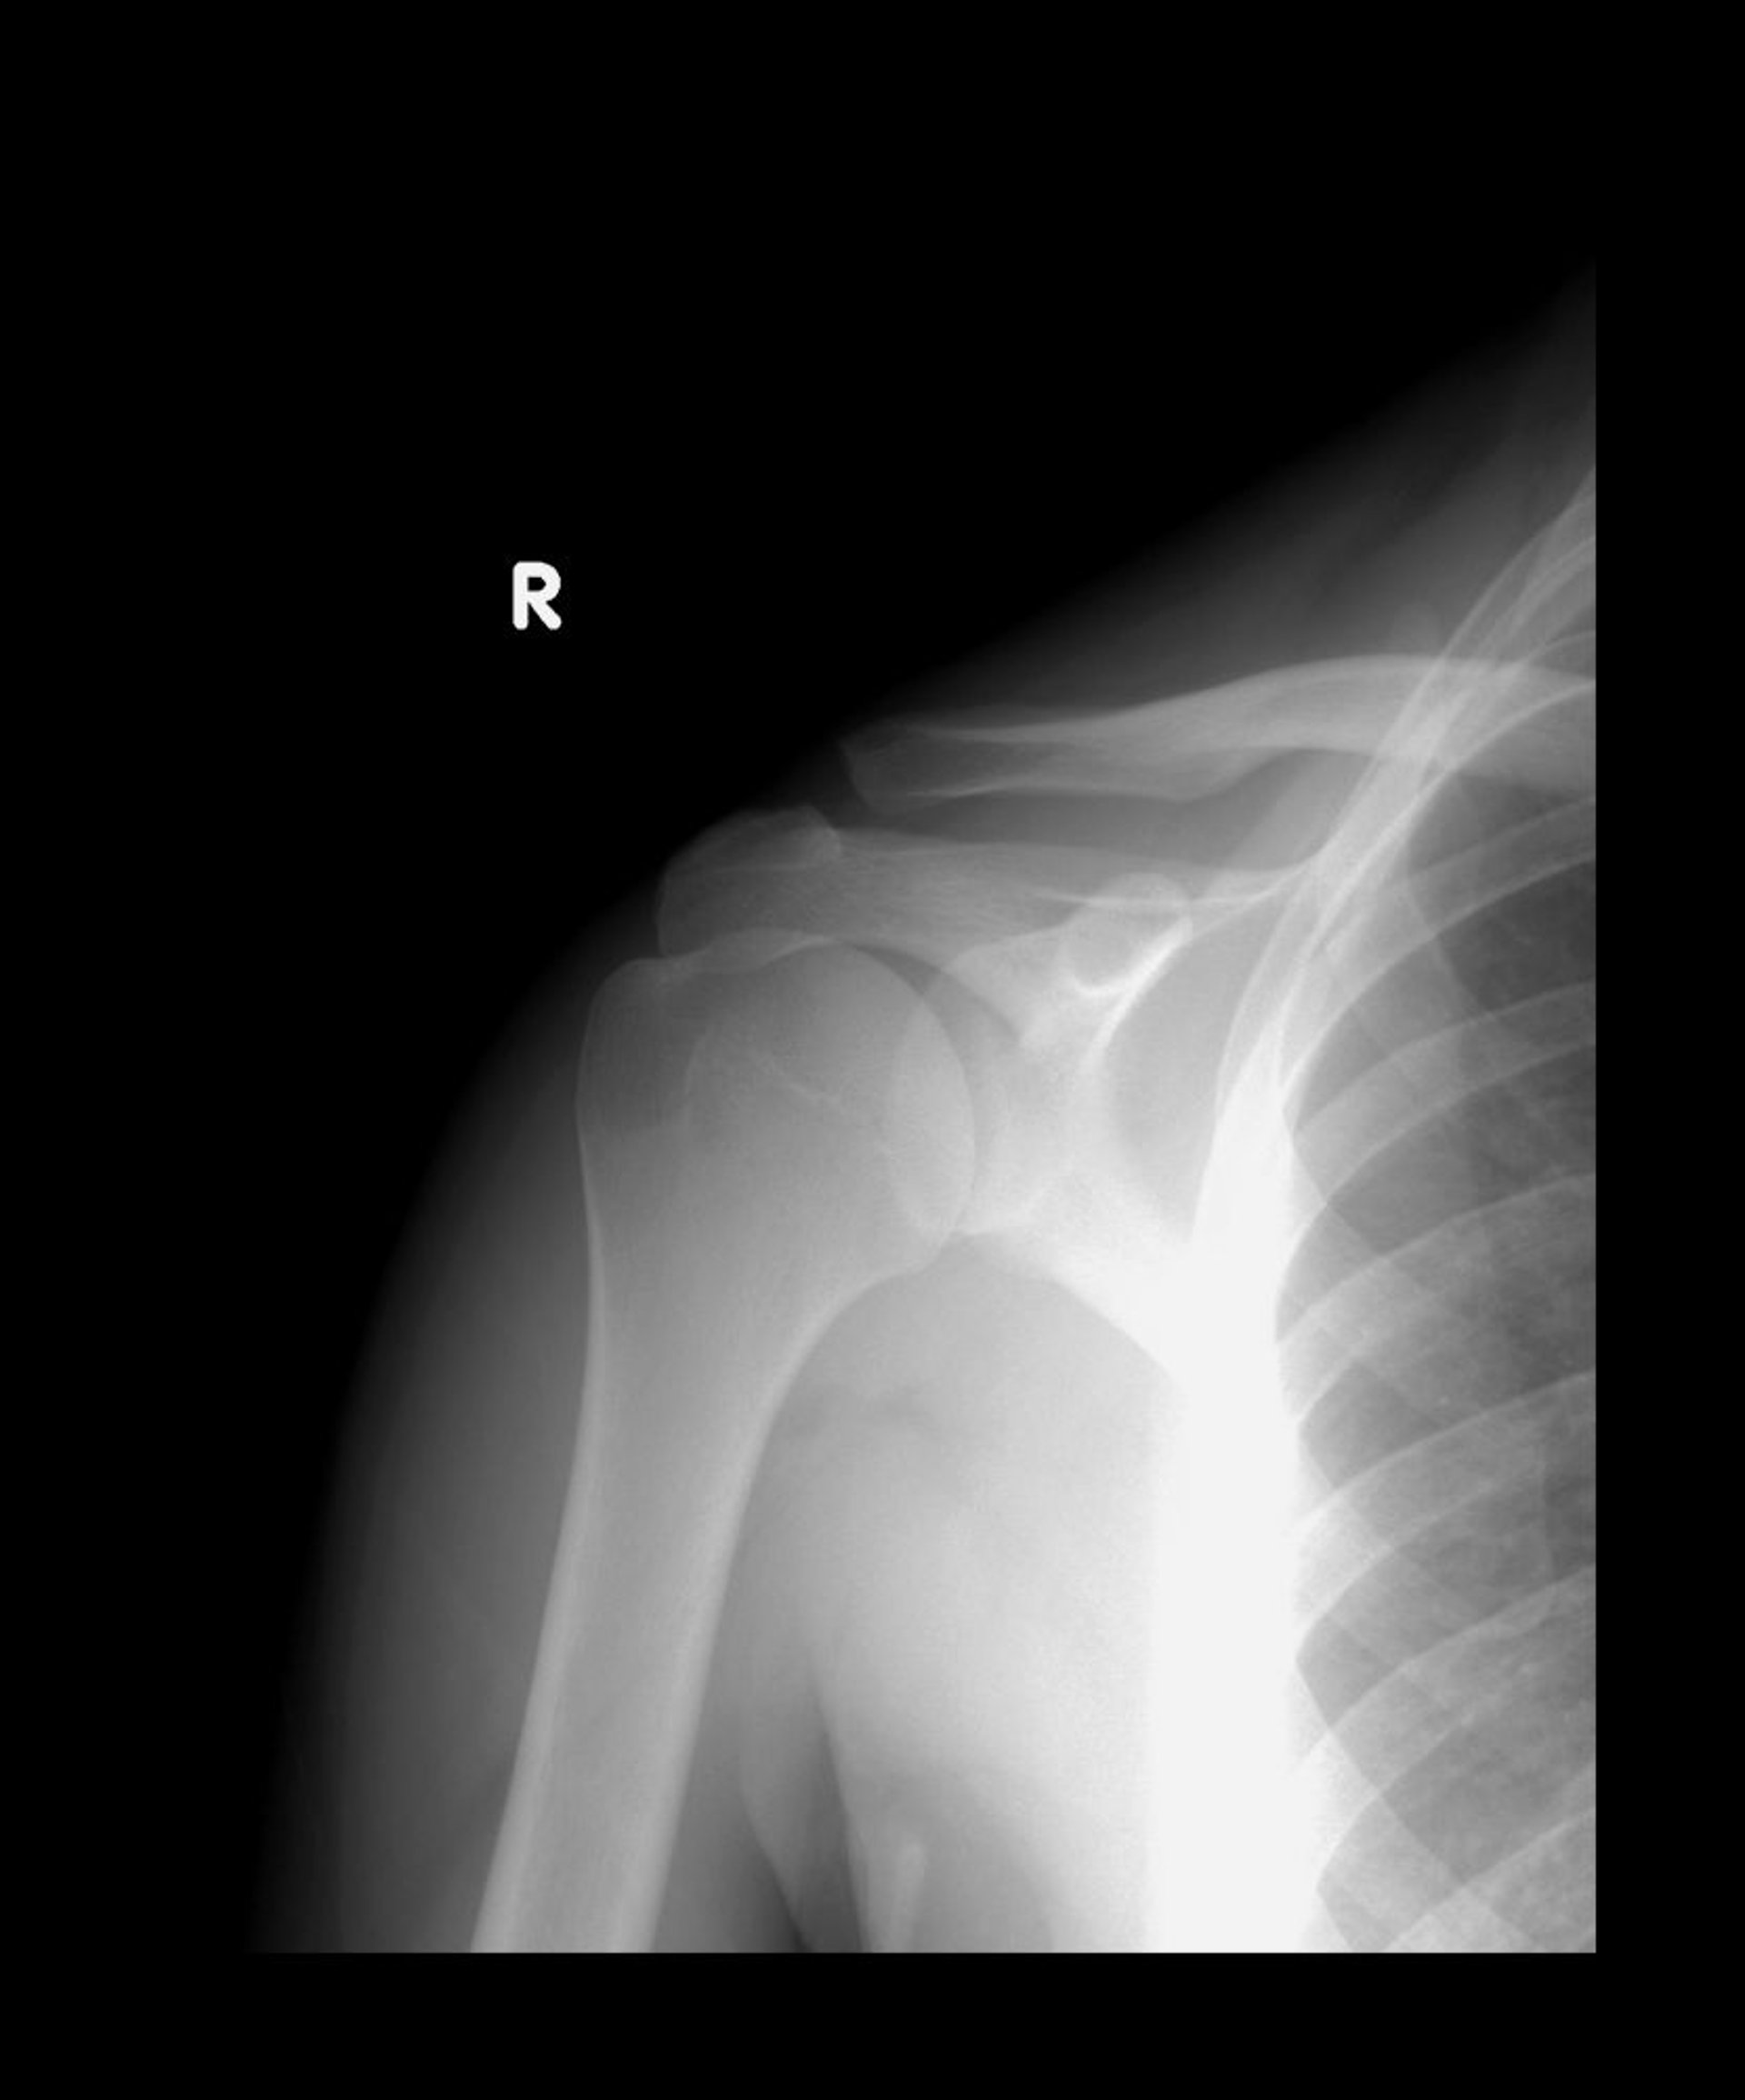

Растяжения связок акромиально-ключичного сустава

Как правило, нижние концы акромиального и ключичного сустава совмещены. На этом рентген-снимке, ключица смещена вверх, но 2 кости все еще перекрывают друг друга, что позволяет предположить подвывих II-го типа.

LIVING ART ENTERPRISES, LLC/SCIENCE PHOTO LIBRARY